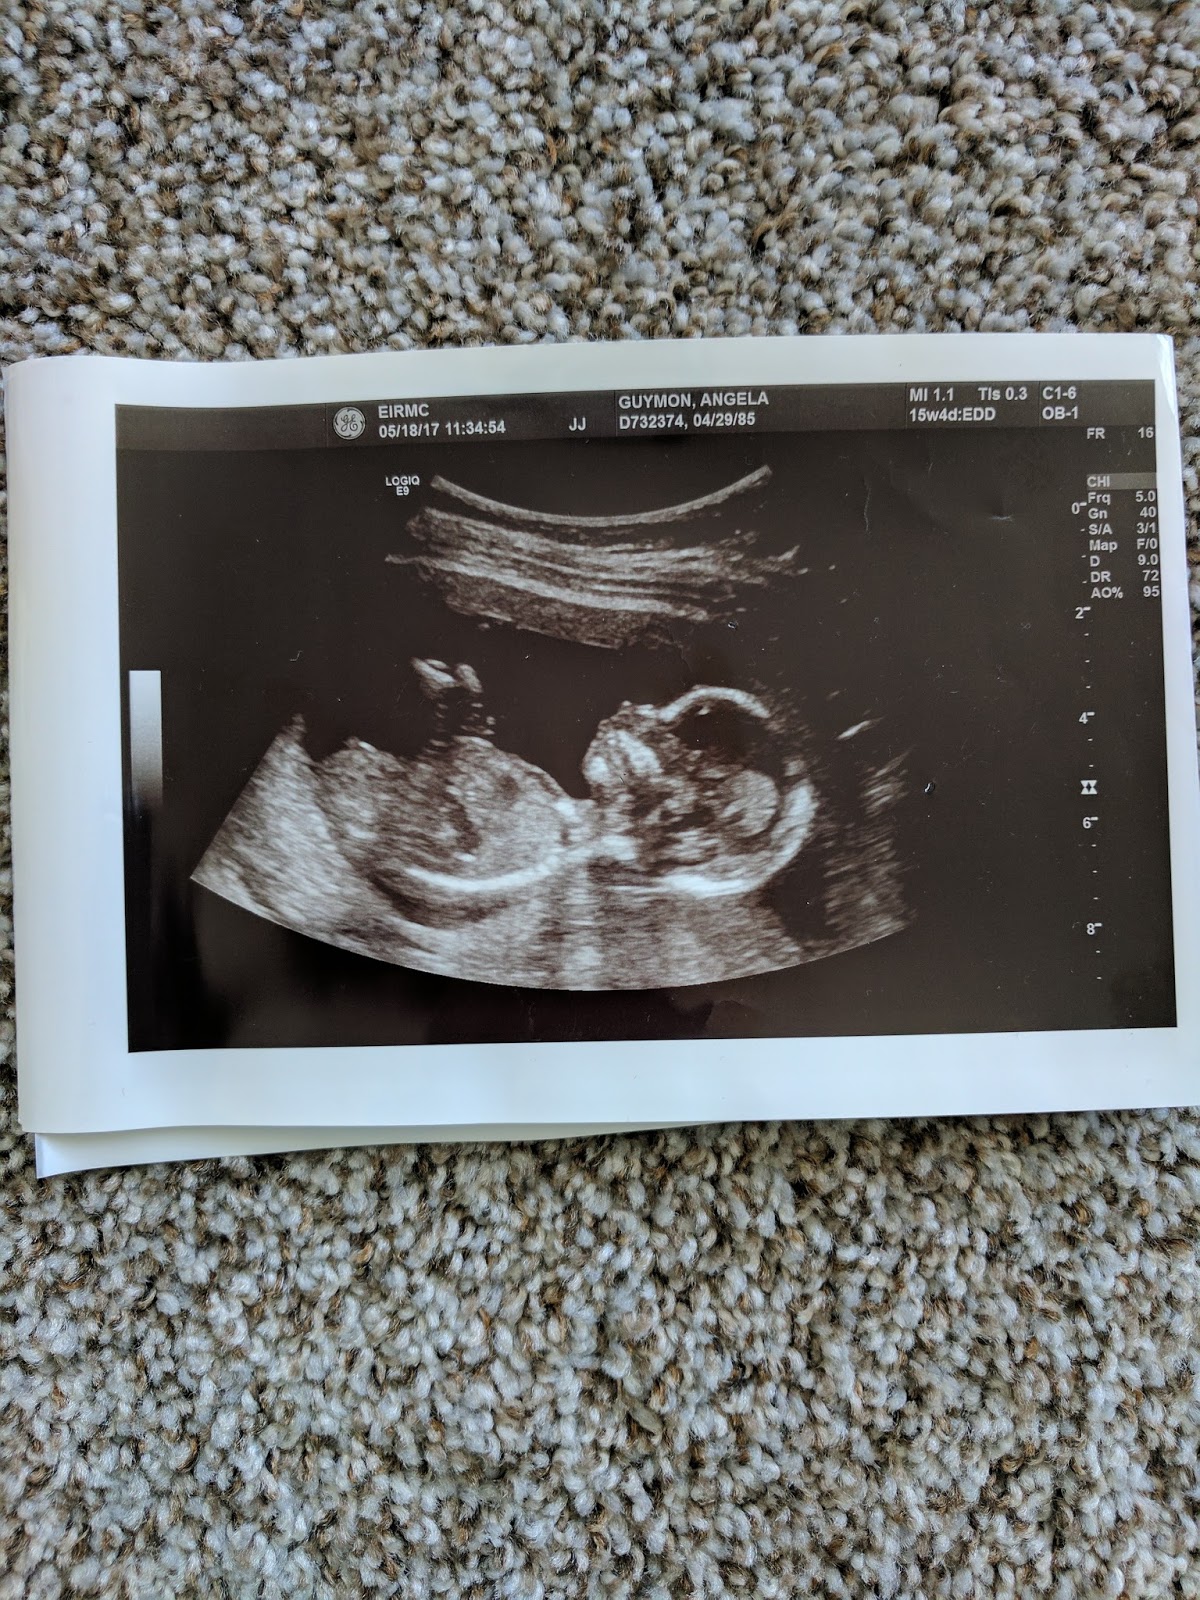

My baby has grown so much it's crazy. Every time I do an ultrasound I'm amazed at the miracle of it all. The baby sure moves and bounces around like crazy every u/s too. I haven't felt any kicks or anything yet but when I do I'm sure it'll be non-stop with how much baby moves.

The u/s showed baby still healthy and strong (huge relief) and that I had a blood clot right above my cervix, the placenta had moved away from the cervix just barely and my cervix had shortened to 2.1cm. It was around 3.4cm at the appoinment on Tuesday. They called to tell Dr. Denson the results and he said he would call Dr. Ball at perinatal office to discuss doing a cerclage (stitching my cervix). I had some cramping around 1:30 that scared me a bit but they said it was probably due to the bleeding and clot and irritation to cervix and uterus. Dr. Denson scheduled the cerclage for 4PM and I had to not eat or drink anything until then.

Dr Denson checked in the next morning and said my blood count was low so put me on iron. They did another u/s while he was there and showed that my cervix still looked around same length as the day before with the stitch which he was pleased with. They told me bed rest through the weekend and would reassess at my appointment Monday with perinatal doctors.